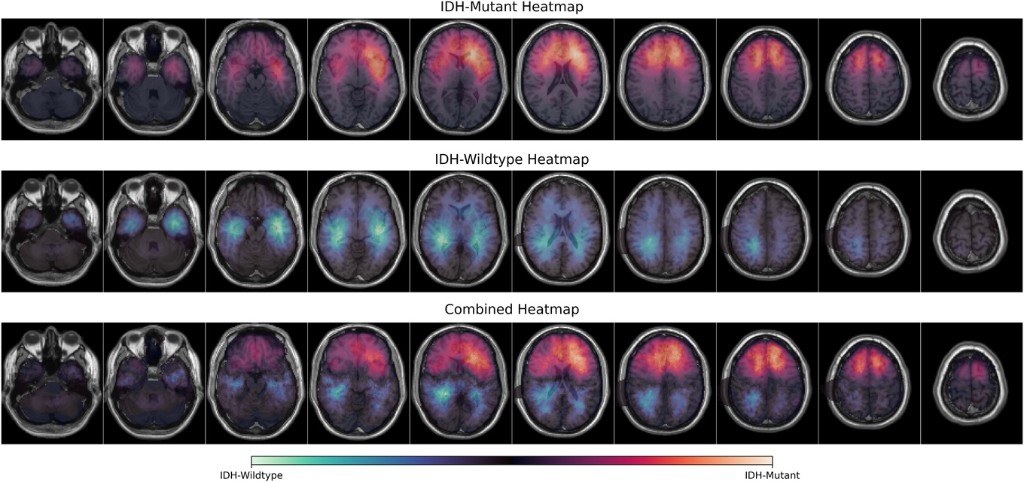

1. Park M, Weiss H, Harake ES, Fang C, Springer A, Goff NK, Markert JE, Reinecke D, Maarouf N, Heiland DH, Miller AM, Todd C. Hollon, John G. Golfinos, and Daniel A. Orringer

NEUROSURGERY · 2026

A multi-institutional spatial analysis characterizing where IDH-mutant gliomas arise in the brain, informing surgical planning, sampling, and interpretation of tumor biology across centers.